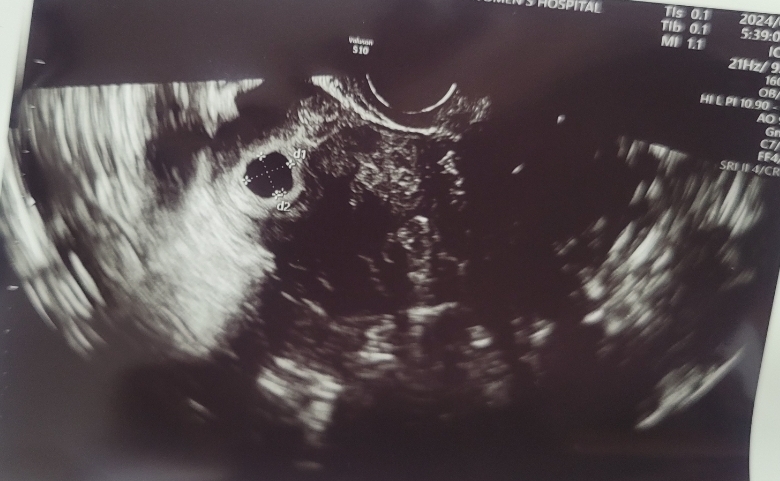

5주5일 아기집 확인, 난황이 안보여서 걱정 되어요

오늘 어플로는 5주4일 병원에서는 5주5일이라고 하네요~ 설레고 두근두근 하는 마음으로 처음 병원을 방문해서 질초음파 했어요 아기집은 보이는데 난황이 안보여서 다음주에 다시 오라고 하네요 ㅠㅠ 괜히 검색해보고 겁이나기 시작했어용.. 난황 다음주 가면 보일까요? 맘이 싱숭생숭 하네요 힝..

설 후 다음주 화요일날 오라고 하시네요 첨이라 궁금하고 설레는 맘이였는데 괜시리 겁도나고 긴장도 되고 그러네요 아기집크기는 사진보니까 1.06cm 0.94cm 되어있네요 다음주 다시 걱정보다 설레는 마음 갖도록 노력해봐야겠어용 우리 화이팅해요!